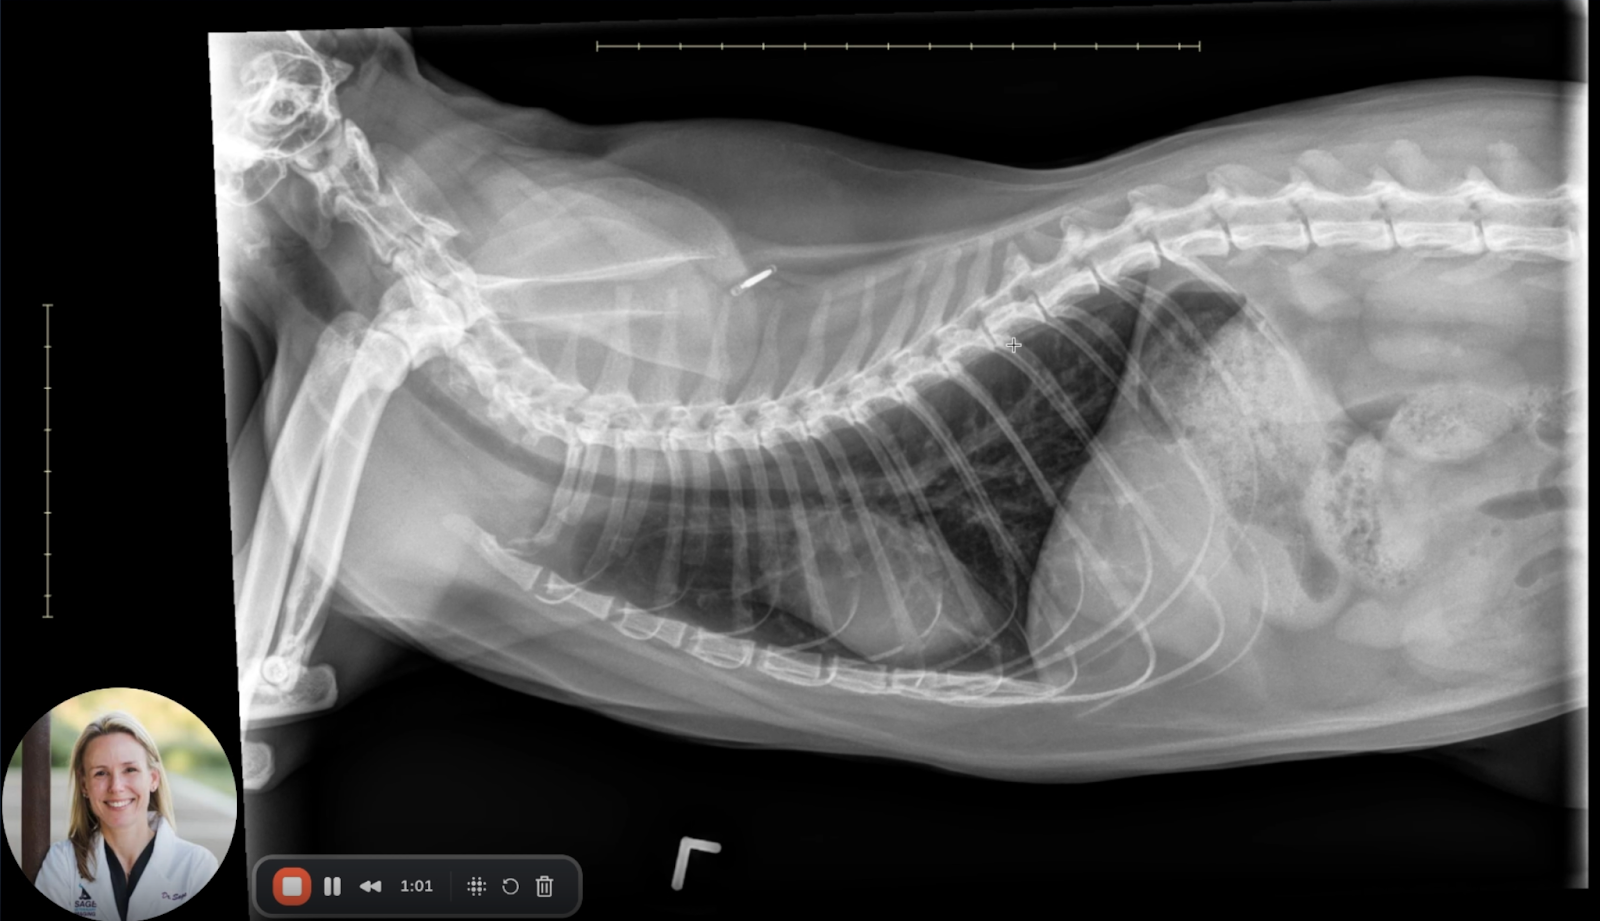

Image 2: Left Lateral View

• Bronchial Pattern: Widespread bronchial thickening is confirmed across both cranial and caudal lung lobes. Peribronchial cuffing is visible without evidence of bronchial plugging or alveolar pattern development.

• Pulmonary Vasculature: Pulmonary arteries and veins are symmetric and within normal diameter ranges, effectively ruling out pulmonary hypertension or overcirculation.

• Cranial Abdomen: The stomach and visualized kidneys are unremarkable, with no evidence of hepatomegaly, masses, or gastrointestinal obstruction.